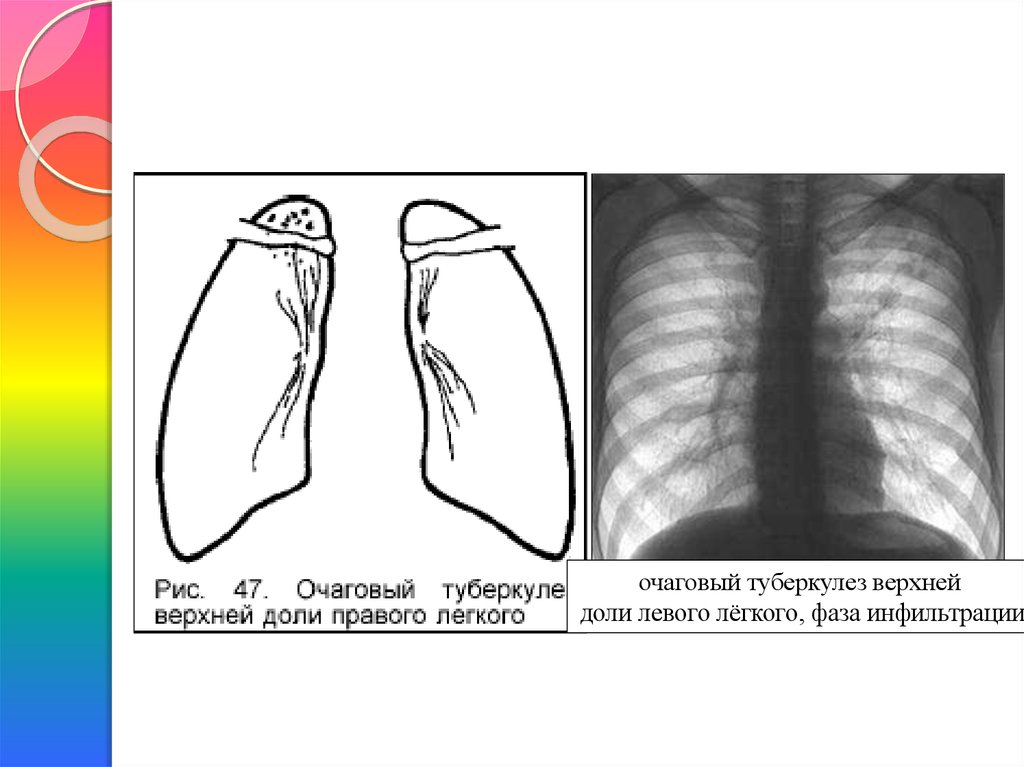

Очаговый и инфильтративный туберкулез презентация - 94 фото